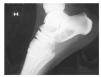

Se realiza estudio radiográfico simple en la misma revisión y se observa imagen radiolucente en cuello de calcáneo con trabéculas óseas en su interior (fig. 1).

Figura 1 Lesión radiolúcida de bordes bien definidos con trabéculas gruesas en su interior localizada en el cuerpo-cuello de calcáneo.